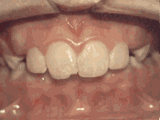

Sparse dentition, with certain teeth congenitally missing, resulting in a sparsely aligned dentition with scattered gaps, affecting aesthetics and occlusion. After orthodontic treatment, the result of the teeth is as follows: